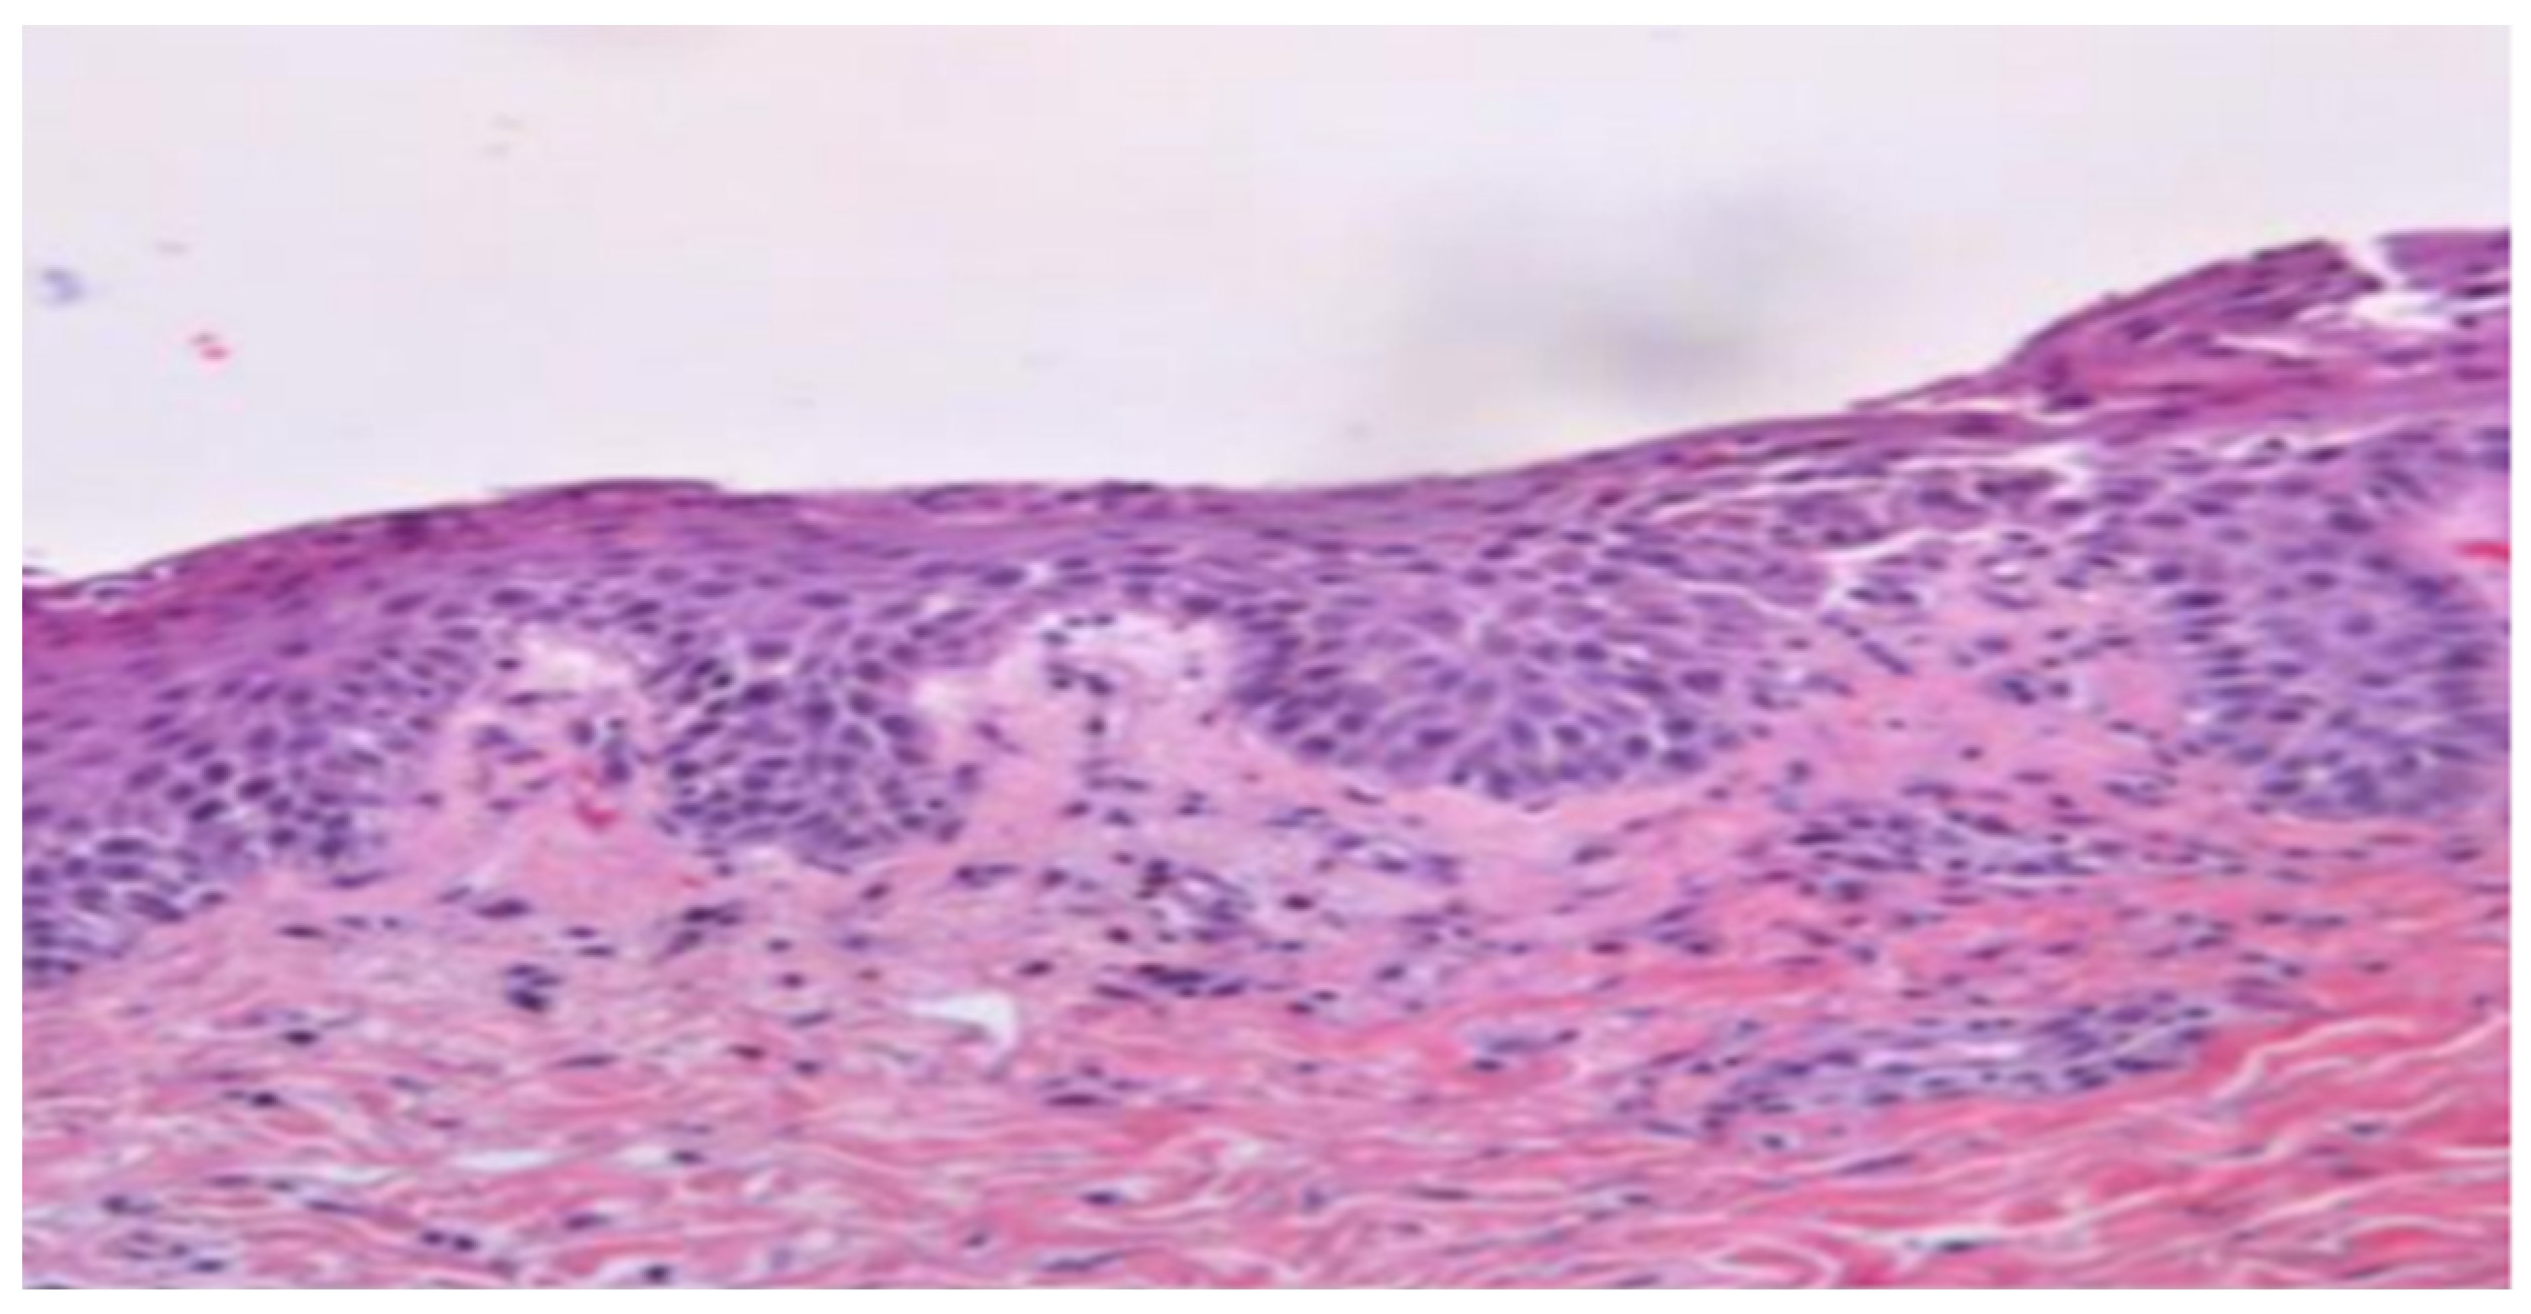

2. Case Presentation